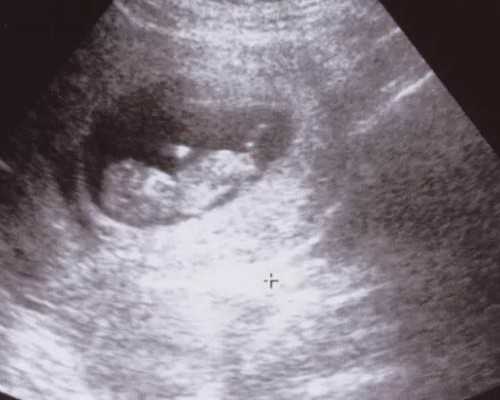

(在这里说下。好多人说打黄体酮很疼,因为都是油,我一点感觉都没有,打针的护士也很友好,一边打一边揉,后来有个护士说可能因为我胖,比较好吸收,哈哈哈,第一次感觉胖也有好处)打了一周的黄体酮今天又去复查了,查b超之前很紧张,就怕没有胎心胎芽,进去之后查了没多久,就和我说挺好的,胎心胎芽都有了,真的超开心,出来在门口等单子的时候就赶紧给老公发消息,这么多天,终于有件开心的事情了!下午孕酮结果也出来了,25,医生看了说挺好的,让回家等着,12周去建档在整个期间,没有过出血,从9月12号开始有孕反,心慌,不想吃东西,每天只要刺激性不大,什么能吃的下去吃什么,也不吐!